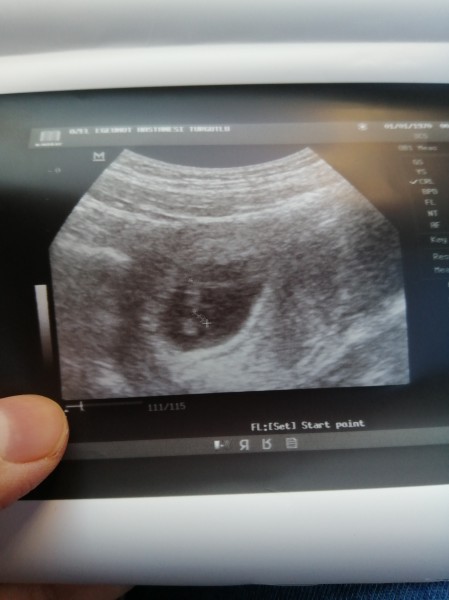

Bugün Allahıma şükürler olsun kalp atışlarını duyduk miniğimin sağ tarafıma yerleşmiş ama doktorum dediki 7+1 günlük ama programa göre 7+5 sıkıntı olmaz demi :unsure:

Gebelik haftası 7+5